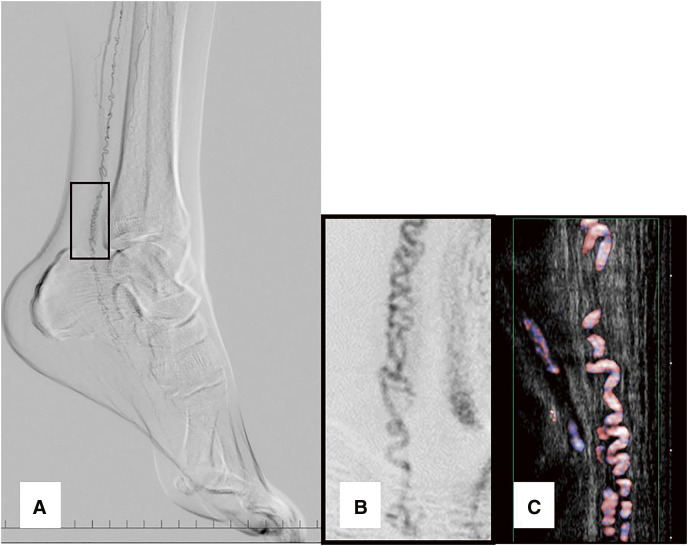

目的:据报道,血栓闭塞性脉管炎(Buerger 病)是一种难治性血管疾病,表现为远端动脉血栓形成,偶尔出现静脉闭塞,血栓和血管壁出现炎性变化。患者往往因肢体坏死而需要截肢。开瓶器(CS)是一种小动脉盘绕,是一种重要的诊断发现,主要通过血管造影发现。不过,最近也可以通过现代超声波技术发现它。方法:在 48 个研究区域的 22 个病例中,我们使用超声波技术识别 CS,从而观察其与周围神经和动脉的关系。结果:在所有病例中,我们都能确定 CS 的位置:在所有病例中,我们都能很容易地识别出 CS,并确认 CS 和神经都被带入鞘中。CS 的位置存在于闭塞的主动脉周围以外的区域,一些 CS 在神经内部(16 个区域),一些 CS 在神经外部(10 个区域),这表明 CS 作为侧支供血血管起作用,具有发达的正常血管样解剖结构。结论我们在观察 CS 时,不仅要观察主干动脉周围,还要观察神经主要流经的区域,即使它们没有伴随主干动脉。(本文译自 Jpn J Vasc Surg 2023; 32: 345-350)。

Objective: Thromboangiitis obliterans (Buerger disease) is known as an intractable vascular disease that has been reported as thrombosis in distal arteries and occasional venous occlusion, as well as inflammatory changes in the thrombus and vascular wall. Patients often require limb amputation due to limb necrosis. Corkscrew (CS), a small arterial coiling, is an important diagnostic finding that was mainly found with angiography. Recently, however, it can also be identified using a modern ultrasonographic technique. Methods: In these 22 cases, in 48 areas of study, we used the ultrasonographic technique to identify the CS, which allowed us to observe its relationship with the surrounding nerves and arteries. Results: In all cases, it was possible to identify the CS easily and it was confirmed that the CS and the nerve were carried down in their sheath. The sites of the CS existed in areas other than the area around the occluded main arteries and some CS that ran inside the nerve (16 areas) and some CS that accompanied the outside of the nerve (10 areas) were confirmed, suggesting the CS work as collateral blood supply vessels, with well-developed normal vessel-like anatomy. Conclusion: When we observe the CS, it is important to observe not only around the main trunk artery but also areas where nerves mainly run, even if they do not accompany the main trunk artery. (This is a translation of Jpn J Vasc Surg 2023; 32: 345-350.).